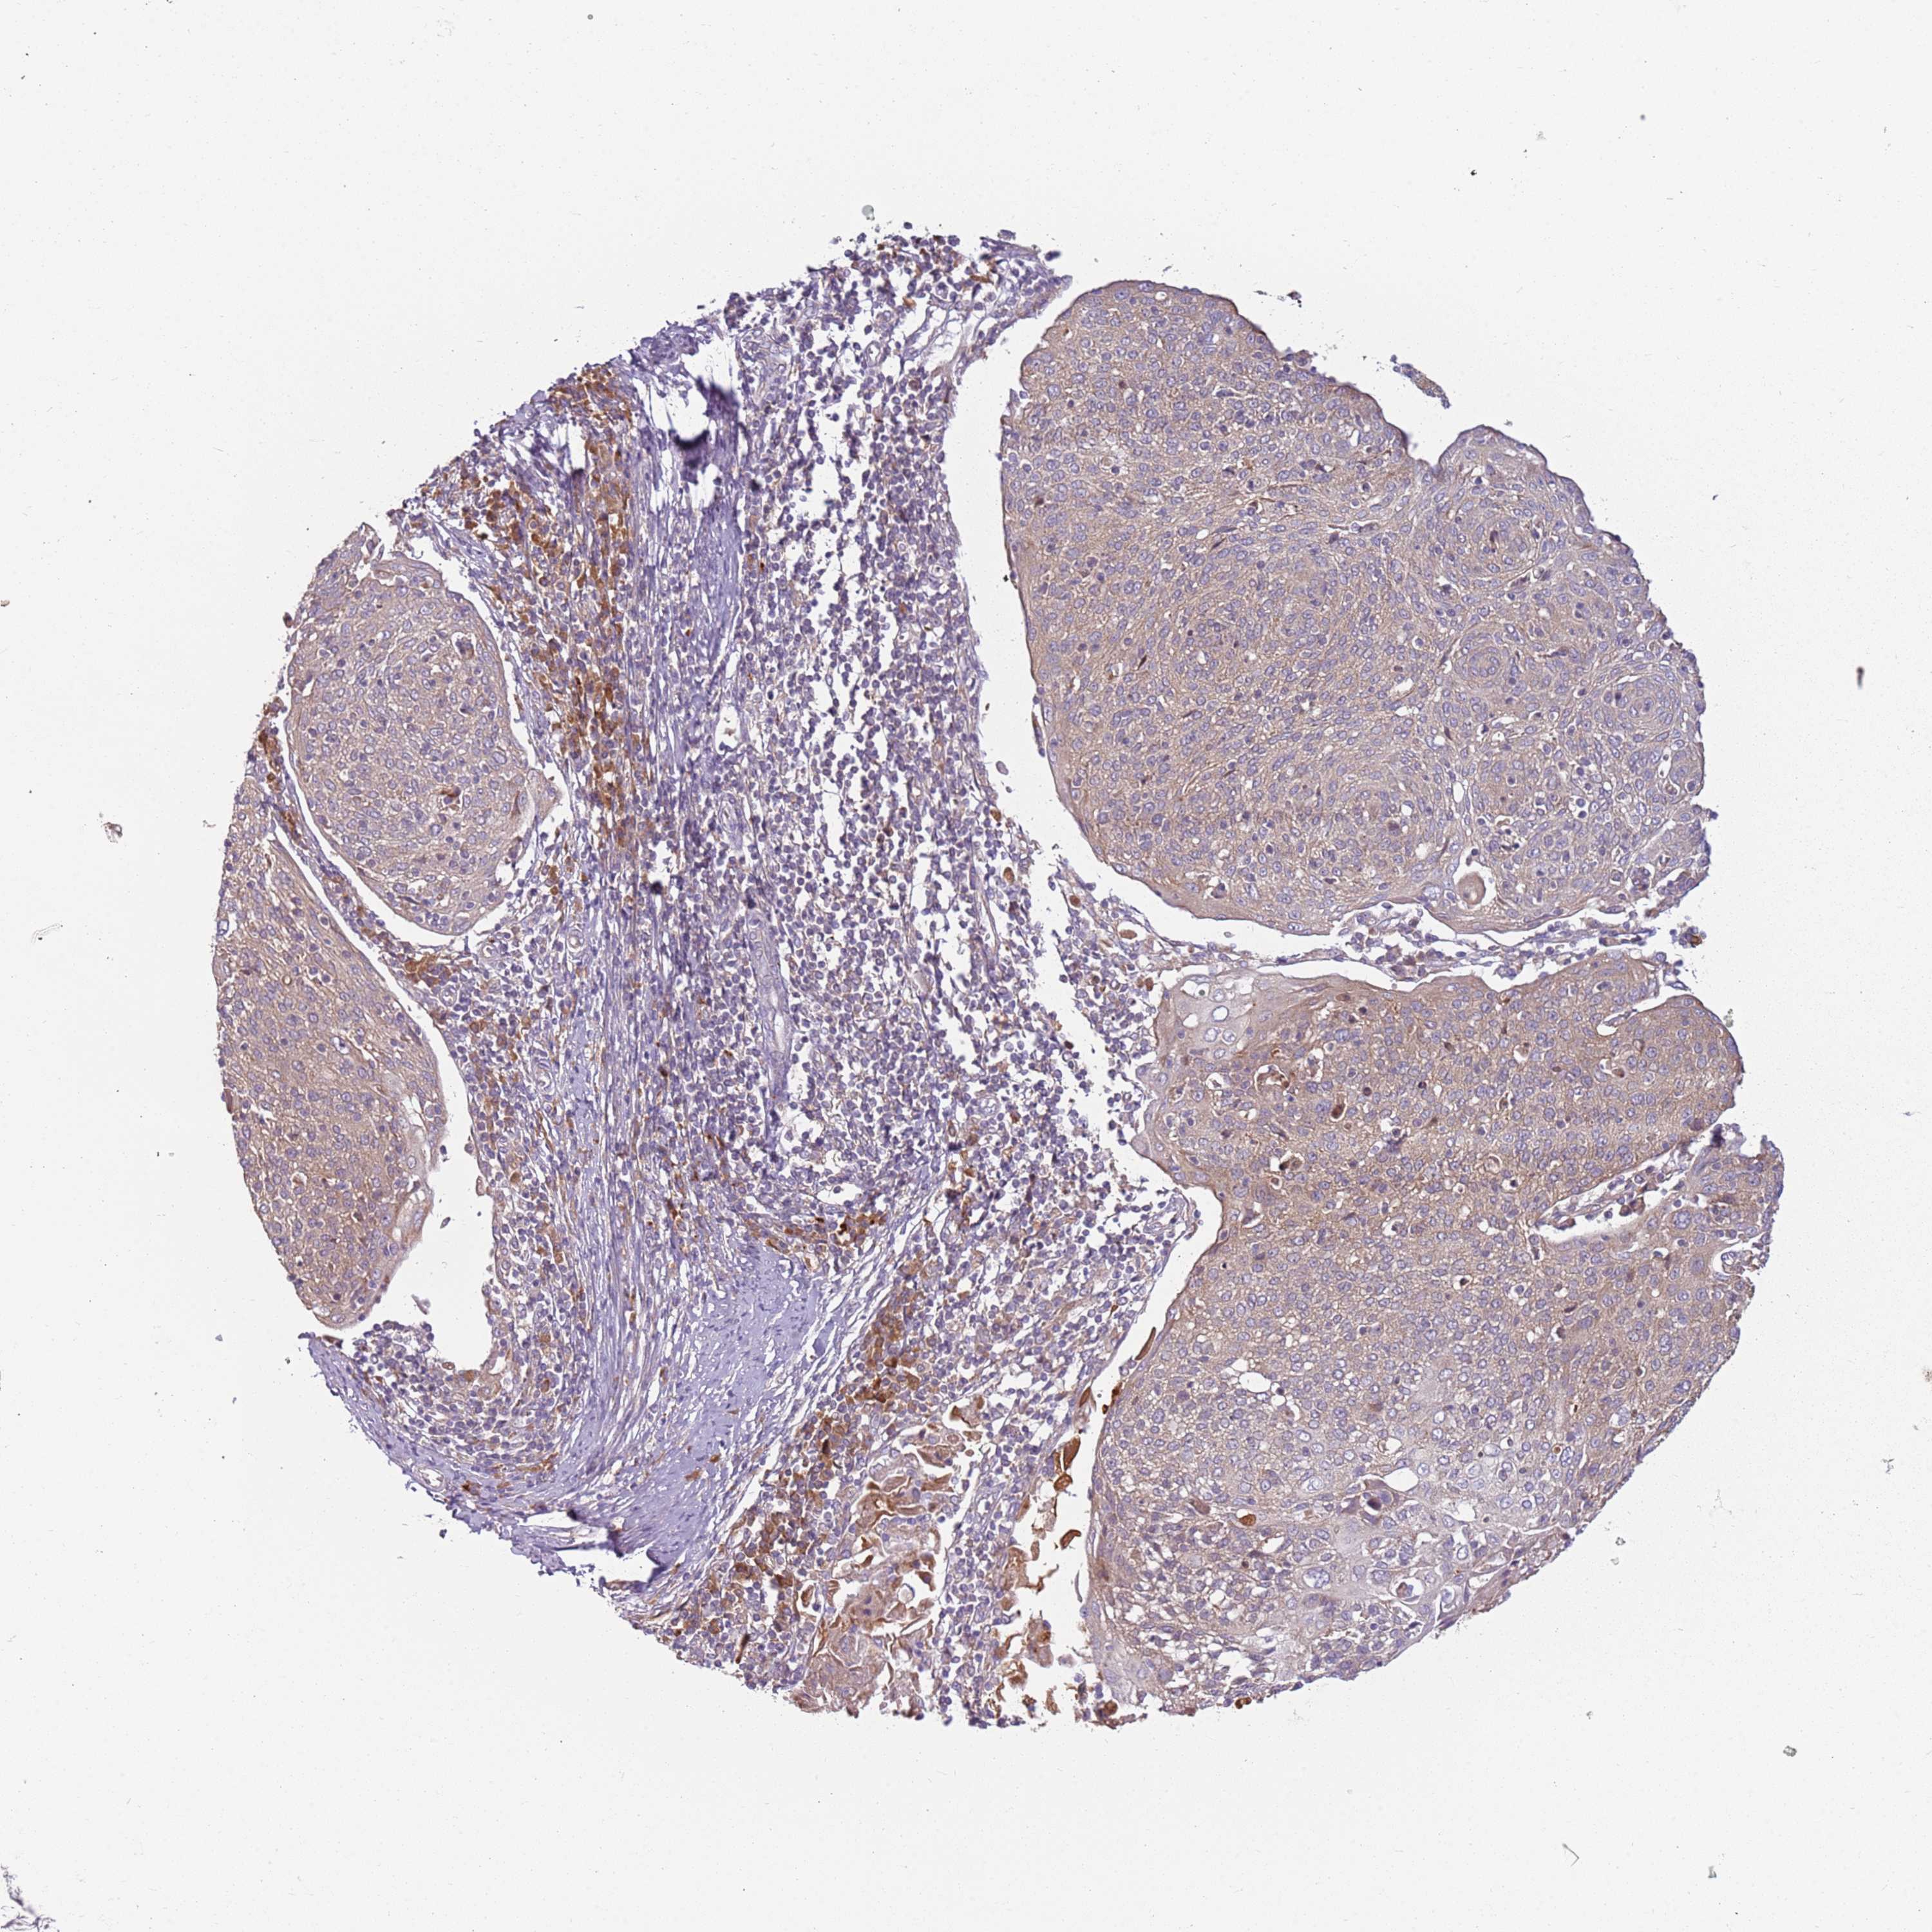

CERVICAL CANCER - Protein expressioni

A mouse-over function shows sample information and annotation data. Click on an image to view it in a full screen mode. Samples can be filtered based on level of antibody staining by selecting one or several of the following categories: high, medium, low and not detected. The assay and annotation is described here.

Note that samples used for immunohistochemistry by the Human Protein Atlas do not correspond to samples in the TCGA dataset.

Antibody stainingi

Antibody staining in the annotated cell types in the current human tissue is reported as not detected, low, medium, or high, based on conventional immunohistochemistry profiling in selected tissues. This score is based on the combination of the staining intensity and fraction of stained cells.

Each image is clickable and will lead to virtual microscopy that enables deeper exploration of all samples and also displays staining intensity scores, fraction scores and subcellular localization as well as patient and tissue information for each sample.

Antibody HPA047132

Staining

High

Medium

Low

Not detected

Intensity

Strong

Moderate

Weak

Negative

Quantity

>75%

75%-25%

<25%

None

Location

Nuclear

Cytoplasmic/membranous

Cytoplasmic/membranous,nuclear

Squamous cell carcinoma, NOS

Adenocarcinoma, NOS